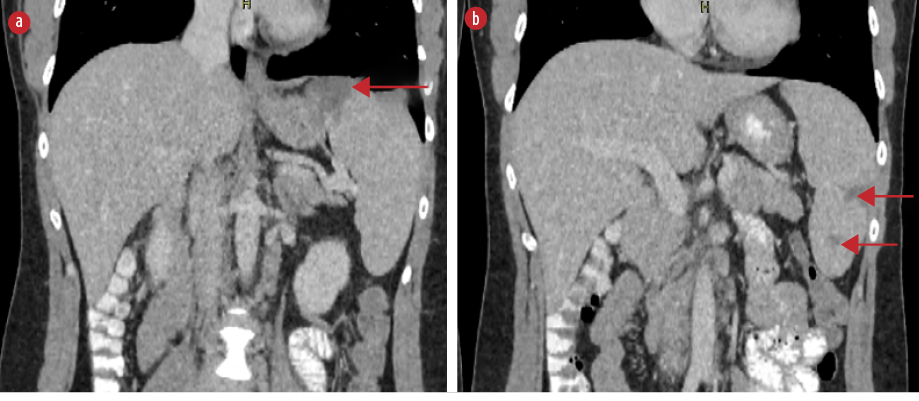

On the fifth day of hospitalization, the patient complained of new-onset left upper quadrant abdominal pain. Clinical examination revealed mild tenderness in the left upper quadrant and a palpable spleen. Computed tomography (CT) of the abdomen with intravenous contrast demonstrated multiple enlarged iliac lymph nodes, hepatomegaly (178 mm in the midclavicular line), and moderate splenomegaly (140 mm in the longitudinal axis). Multiple hypodense splenic lesions were visible without contrast enhancement, suggestive of splenic infarcts [Figures 1 and 2]. CT angiography of the abdomen showed no thrombi in the splenic vasculature. Hypercoagulability workup revealed mildly reduced protein S activity. Molecular testing for inherited thrombophilia (Factor V Leiden, Factor II-prothrombin, Factor XIII, MTHFR, and JAK2 V617 gene mutations) yielded negative results [Table 1]. Transesophageal echocardiography showed no evidence of thrombi, vegetation, or other abnormalities.

Figure 2: Coronal abdominal CT scan with intravenous contrast demonstrating multiple splenic infarcts (red arrows), (a) located at the superior, as well as (b) the middle and lower parts of the spleen.

Abdominal ultrasound is not recommended as the sole imaging modality because of its low sensitivity.6,9,14 The imaging modality of choice is contrast-enhanced CT, on which splenic infarcts commonly appear as wedge-shaped hypodense lesions without post-contrast enhancement after contrast administration.6,7 On magnetic resonance imaging, splenic infarcts are visualized as lesions with low signal intensity on both T1-weighted and T2-weighted images.9 In the present case, abnormal lesions suggestive of infarcts became evident on CT scan with intravenous contrast as wedge-shaped lesions without contrast enhancement.